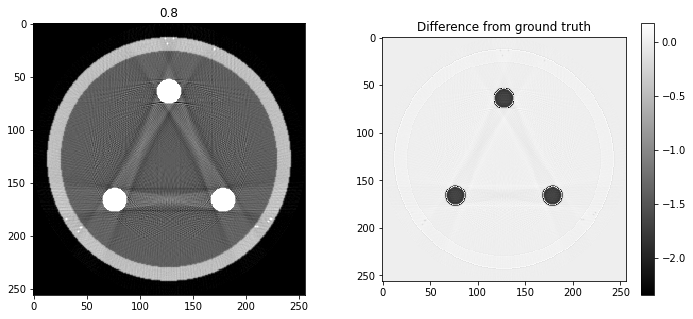

# Question 12

search = np.linspace(0,1,11)

for alpha in search:

rec = out+alpha*reproj

f,ax = plt.subplots(1,2,figsize=(12,5))

ax[0].imshow(rec,vmin=0,vmax=0.5)

ax[0].set_title(alpha)

im = ax[1].imshow(img[80]-rec)

f.colorbar(im,ax=ax[1])

ax[1].set_title('Difference from ground truth')

plt.show()